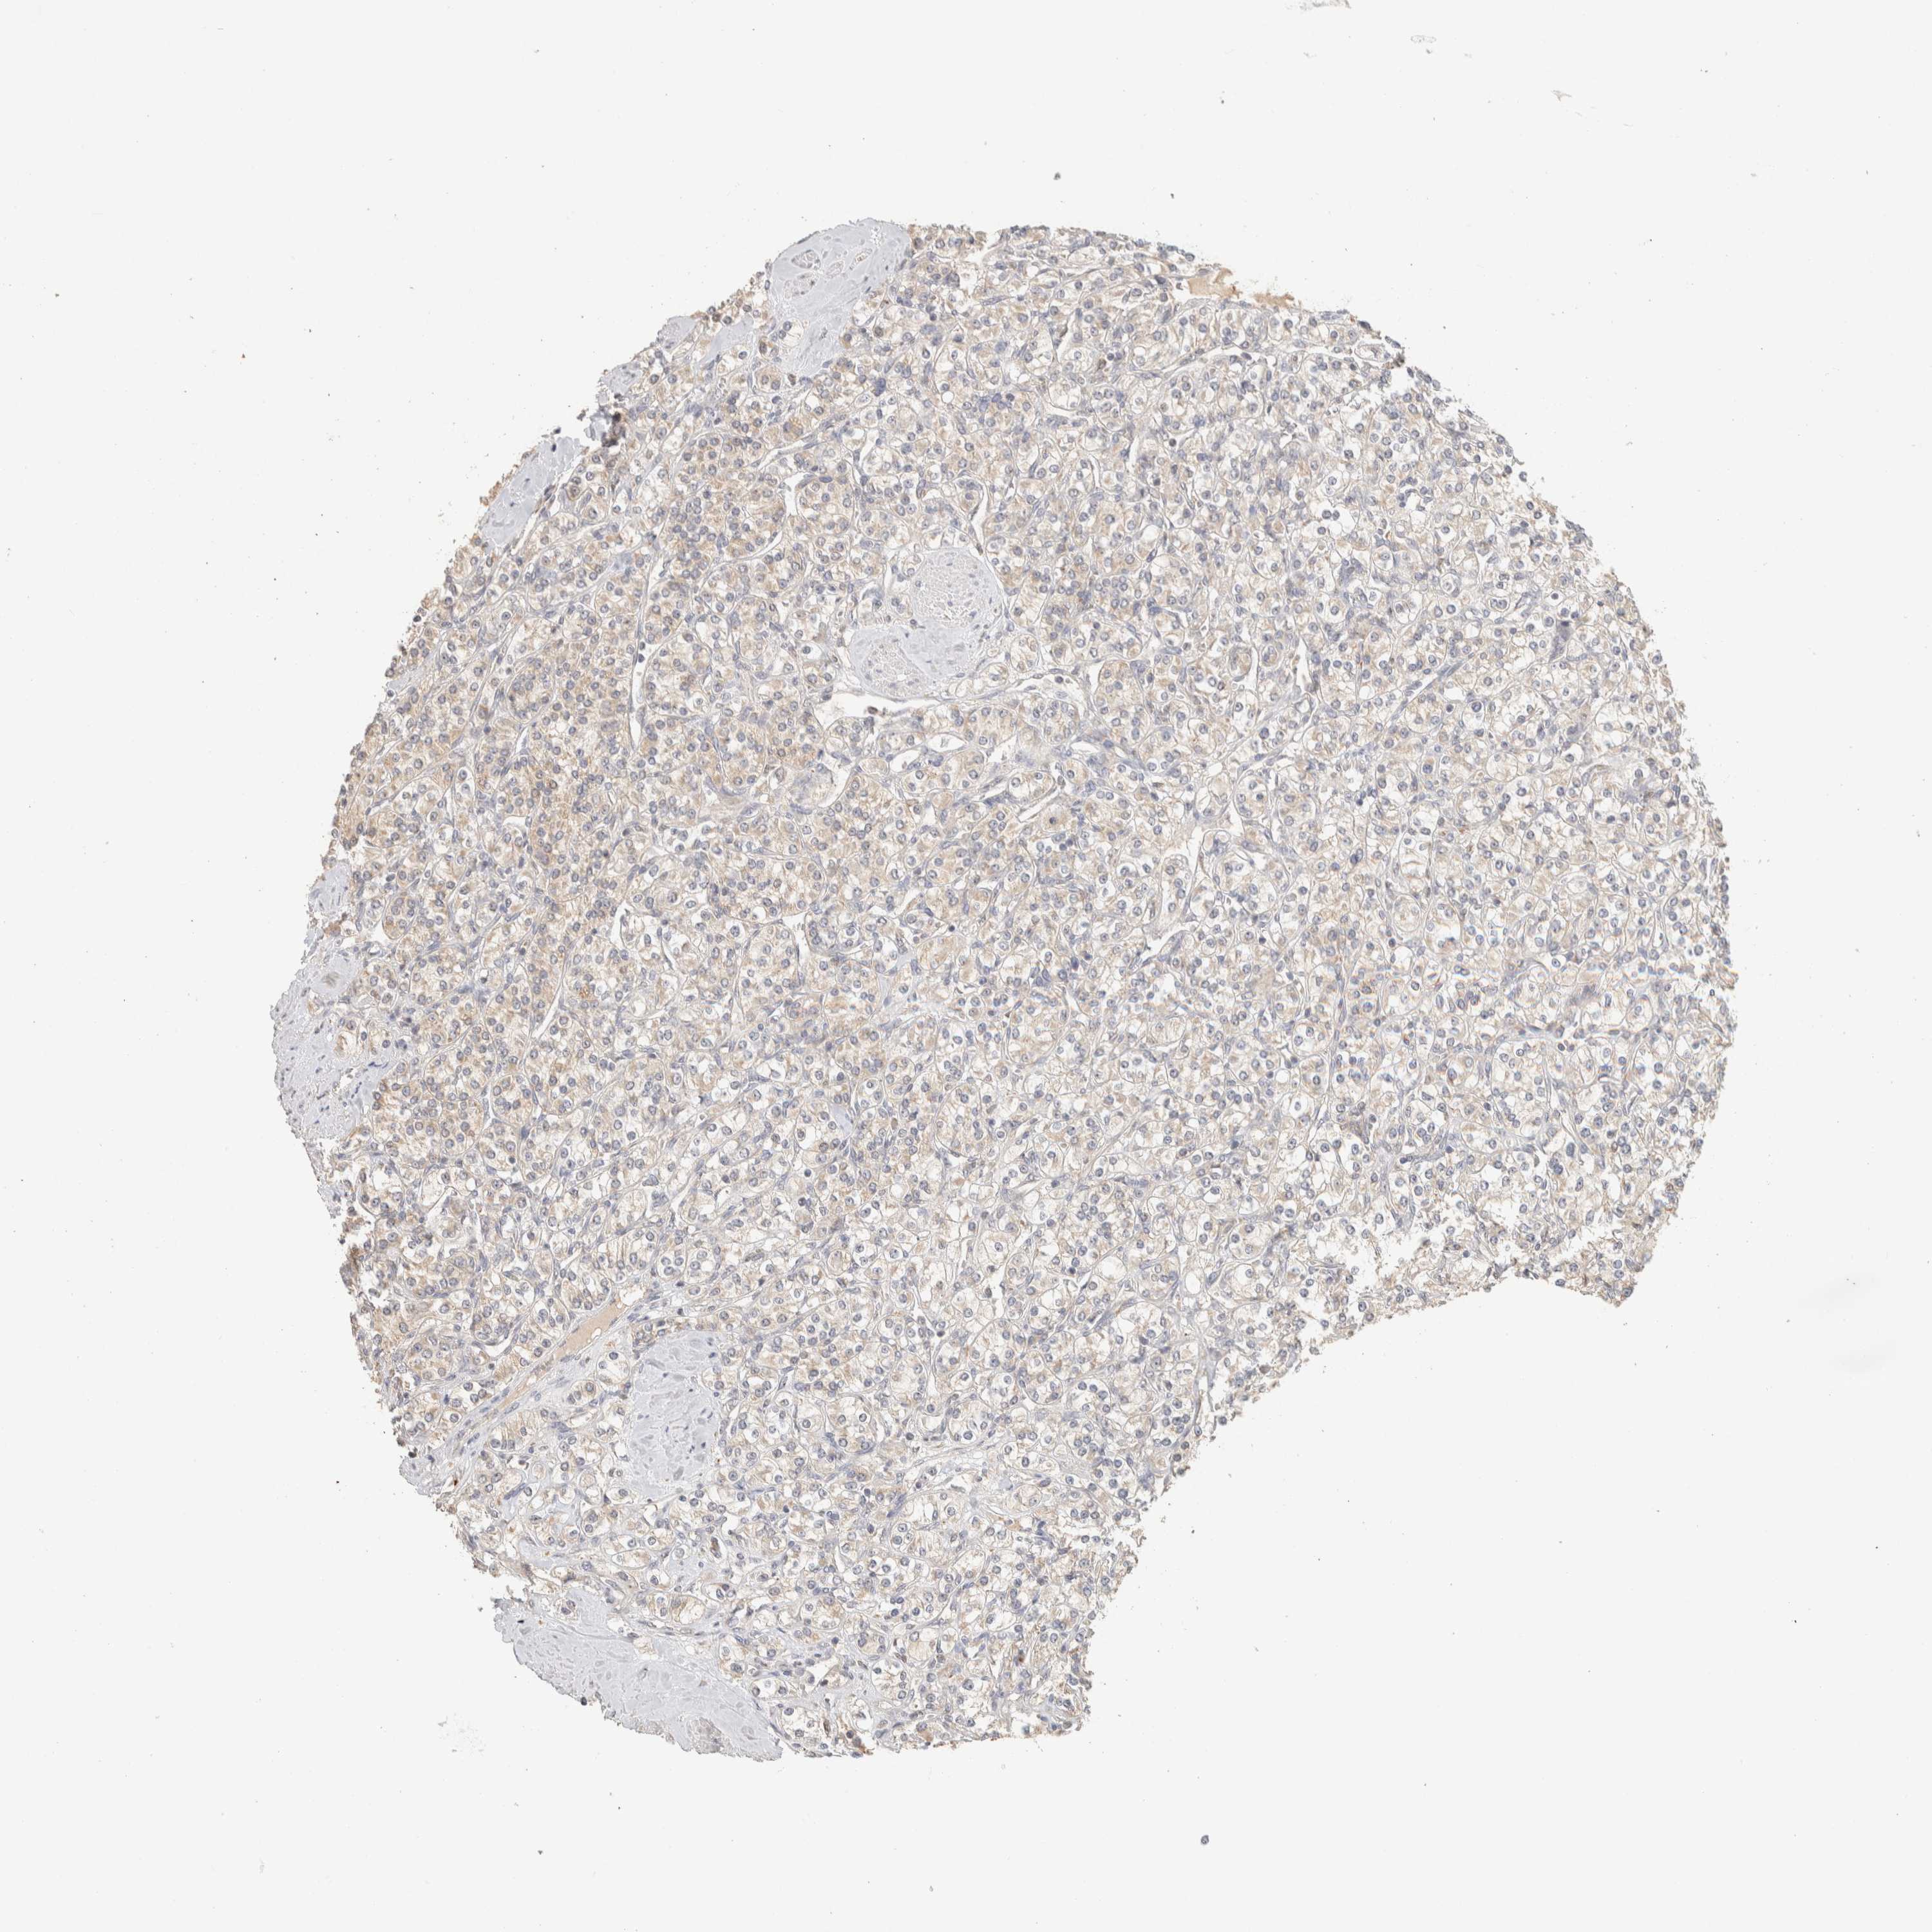

KIDNEY CHROMOPHOBE (TCGA) - Interactive survival scatter ploti

The Survival Scatter plot shows the clinical status (i.e. dead or alive) for all individuals in the patient cohort, based on the same data that underlies the corresponding Kaplan-Meier plots. Patients that are alive at last time for follow-up are shown in blue and patients who have died during the study are shown in red.

The x-axis shows the expression levels (FPKM) of the investigated gene in the tumor tissue at the time of diagnosis. The y-axis shows the follow-up time after diagnosis (years). Both axes are complimented with kernel density curves demonstrating the data density over the axes. The top density plot shows the expression levels (FPKM) distribution among dead (red) and alive patients (blue). The right density plot shows the data density of the survived years of dead patients with high and low expression levels respectively, stratified using the cutoff indicated by the vertical dashed line through the Survival Scatter plot. This cutoff is automatically defined based on the FPKM cutoff that minimizes the p-score. The cutoff can be changed by dragging the vertical line or by entering a cutoff value in the square labeled "Current cut-off".

Under the Survival Scatter plot the p-score landscape (black curve; left axis) is shown together with dead median separation (red curve; right axis). Dead median separation is the difference in median mRNA expression between patients who have died with high and low expression, respectively. It is calculated as follows: median FPKM expression of dead patients with high expression - median FPKM expression of dead patients with low expression. This is intended to aid the user in visually exploring custom cutoffs and the associated p-scores and dead median separation.

Individual patient data is displayed and can be filtered by clicking on one or more of the category buttons on the top of the page. Categories describing expression level and patient information include: high, low, alive, dead, female, male and tumor stages. The scale of the x-axis can be toggled between linear and log-scale by clicking on the "x log" button. Mouse-over function shows TCGA ID, patient information and mRNA expression (FPKM) for each patient.

& Survival analysisi

Kaplan-Meier plots summarize results from analysis of correlation between mRNA expression level and patient survival. Patients were divided based on level of expression into one of the two groups "low" (under cut off) or "high" (over cut off). X-axis shows time for survival (years) and y-axis shows the probability of survival, where 1.0 corresponds to 100 percent.

ITPA is not prognostic in Kidney Chromophobe (TCGA)

Best expression cut offi

Based on the FPKM value of each gene, patients were classified into two groups and association between prognosis (survival) and gene expression (FPKM) was examined. The best expression cut-off refers the FPKM value that yields maximal difference with regard to survival between the two groups at the lowest log-rank P-value. Best expression cut-off was selected based on survival analysis .

When clicking on this number, the vertical dashed line indicating cut-off, the interactive survival plot, and the Kaplan-Meier curve will be adjusted to show results based on the best expression cut-off.

: 60.72

P scorei

Log-rank P value for Kaplan-Meier plot showing results from analysis of correlation between mRNA expression level and patient survival.

N/A

TCGA RNA samplesi

RNA-seq data is reported as average FPKM (number Fragments Per Kilobase of exon per Million reads), generated by the The Cancer Genome Atlas (TCGA) .

Normal distribution across the dataset is visualized with box plots, shown as median and 25th and 75th percentiles. Points are displayed as outliers if they are above or below 1.5 times the interquartile range. FPKM values of the individual samples are presented next to the box plot.

Average pTPM 47.0

Number of samples 64